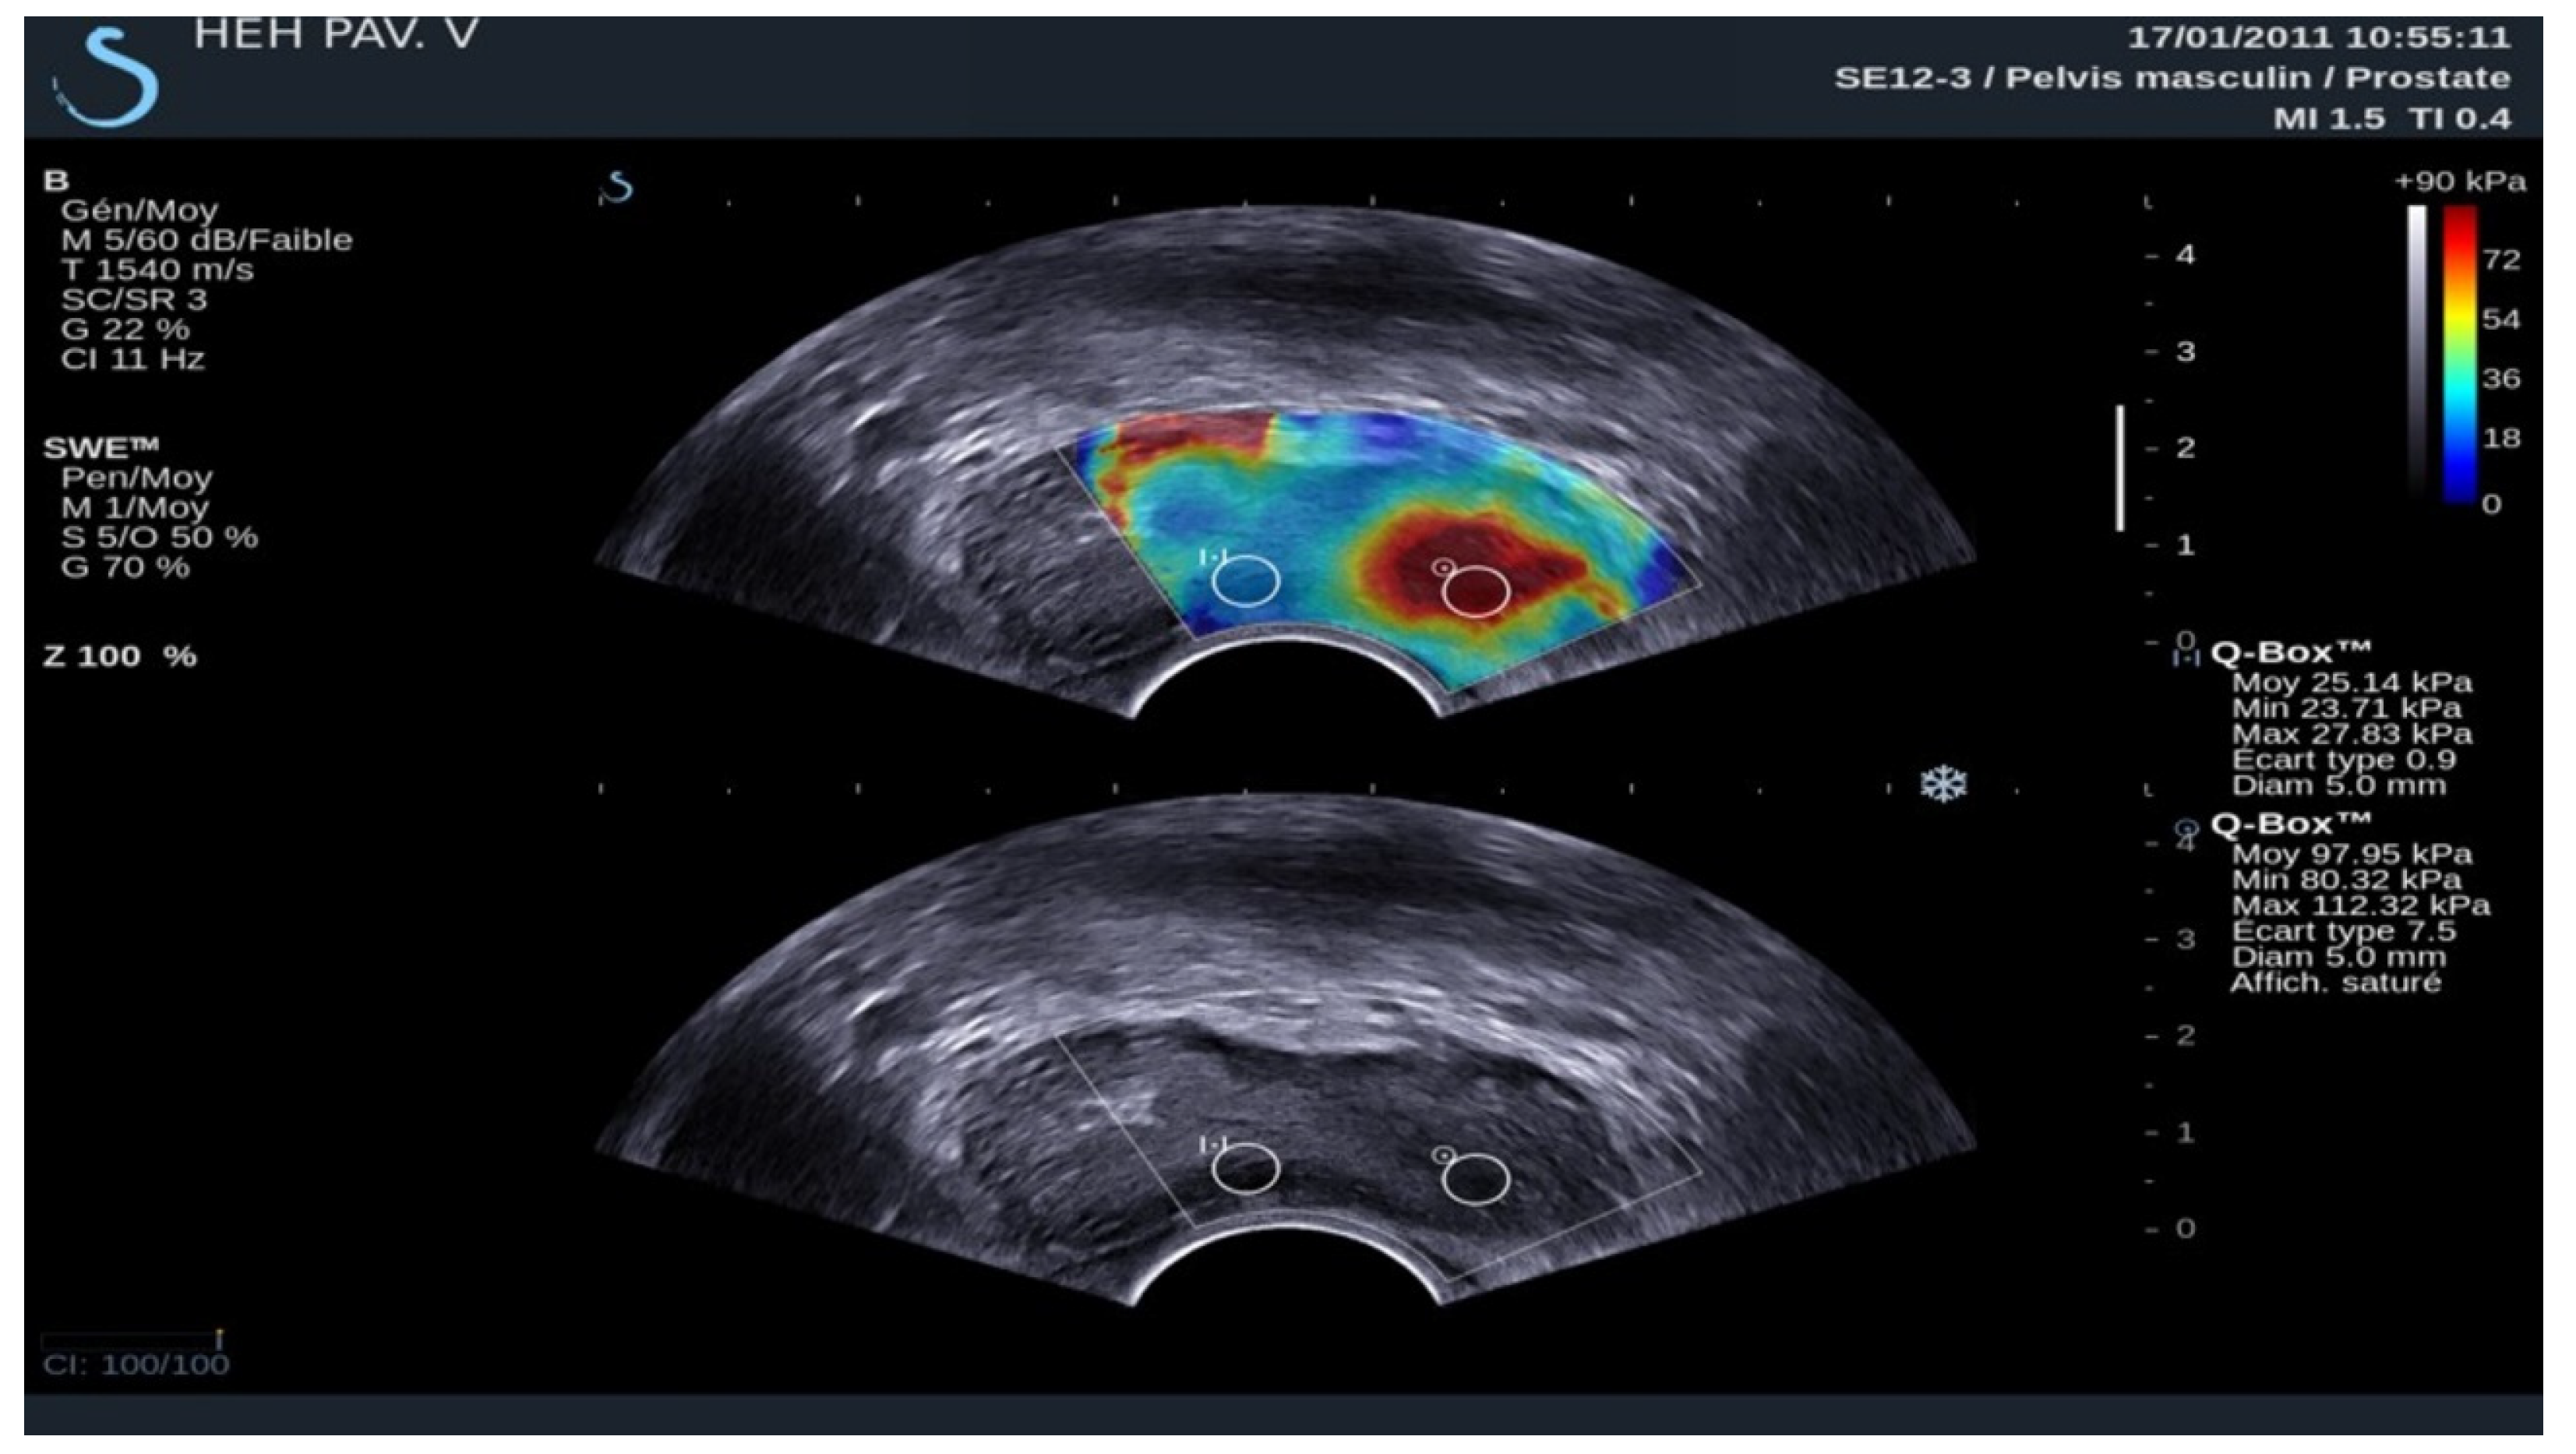

SE was interpreted based on the colour of the area in the elastography map. On the other hand, SWE was interpreted using a cut-off value in kilopascals. The SWE stiffness values in our study were based on transverse (axial) plane imaging (Figure 4 and Figure 5).

Figure 4.

A 65-year-old patient with elevated PSA without other clinical data of interest. Image obtained using a SuperSonic Aixplorer ultrasound scanner with a multifrequency transrectal probe, bandwidth 3–12 MHz. Prostate cancer: the image identifies that the ROI of the left lobe has a mean hardness of 97.95 kPa, which is highly suspicious of malignancy. This finding was subsequently confirmed by biopsy.